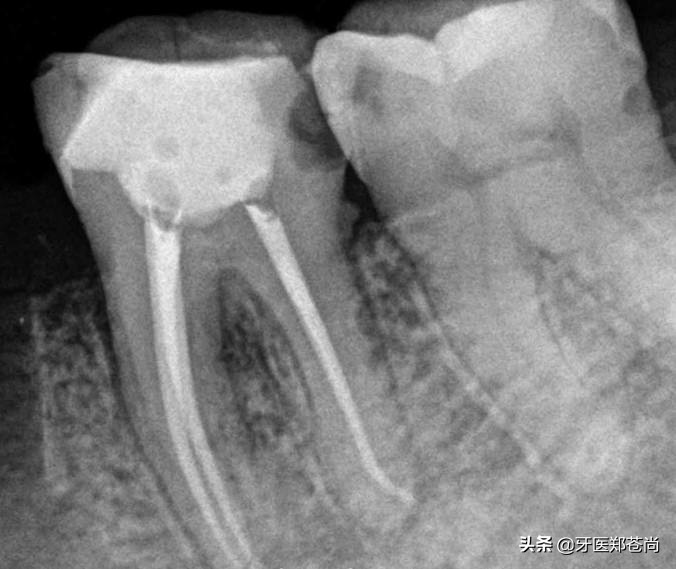

根管治疗是牙体牙髓病的治疗方式,打开牙髓,直达病灶解决问题,但想要完全解决牙齿问题并不仅仅是治疗,治疗后还需要对患牙进行适当的修复,做烤瓷牙或者是嵌体,一方面是为了保护失去牙神经的患牙在以后的吃饭使用中不会崩脆,另一方面是防止外界细菌再进入牙齿内部。

1.根管治疗解除内部问题,之后又做了修复,所以是可以正常使用吃饭的。